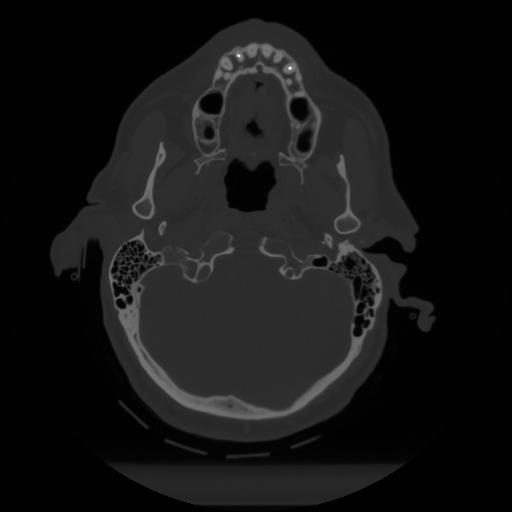

12 P.BLANDAS,,Vol,0.5,P.BLANDAS,,